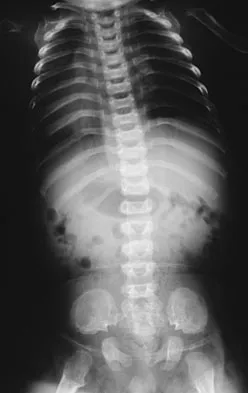

Figures 12a through 12e show the radiograph, MRI scans, and biopsy specimens of a 17-year-old boy. What is the most likely diagnosis?

The images show an epiphyseal lesion. The MRI scan shows extensive bone edema surrounding the lesion, consistent with chondroblastoma. Histology shows polygonal chondroblasts in a cobblestone-like pattern and areas of calcification consistent with chondroblastoma. Although some giant cells are seen, the age of the patient and the polygonal chondroblasts differentiate this lesion from giant cell tumor. Clear cell chondrosarcoma is an epiphyseal lesion that occurs in an older population, and the cells have clear cytoplasm. This lesion is not producing bone on imaging or histologic specimen, eliminating osteosarcoma. Tuberculous septic arthritis can be an epiphyseal lesion, but granulomas would be seen on histology. Menendez LR (ed): Orthopaedic Knowledge Update: Musculoskeletal Tumors. Rosemont, IL, American Academy of Orthopaedic Surgeons, 2002, pp 103-111.